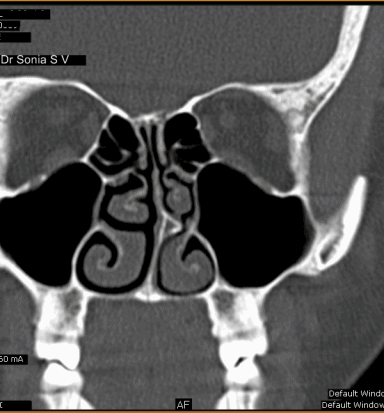

Votre médecin vous questionnera sur vos symptômes et vos antécédents médicaux. Il tapotera des zones de votre visage pour voir si des orifices sinusaux sont sensibles. Une scanographie

peut aussi être utile.

Le type de chirurgie des sinus que votre médecin recommande dépend de votre pathologie. Les trois opérations des sinus les plus courantes sont :

L'éthmoïdectomie – aide à dégager les sinus situés entre vos yeux et l'arête de votre nez.

Méatotomie moyenne (ou maxillaire) – améliore le drainage des sinus situés derrière vos pommettes.

La septoplastie associée à une turbinoplastie – aide à supprimer les difficultés respiratoires causées par une déviation du septum et l'hypertrophie des cornets de votre nez.